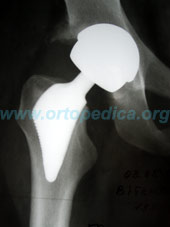

Рентгенограмма после операции